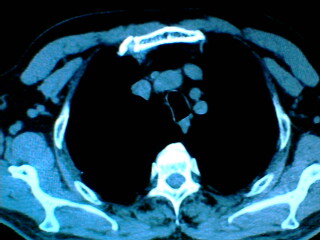

老年男性患者,右侧胸疼1月余(不是左侧),无其他症状

支持肺囊肿,液体含量多,可能与支气管不通.右侧胸膜局限性肥厚,可能是导致痛的原因.

支持肺囊肿,右侧胸膜肥厚粘连钙化.